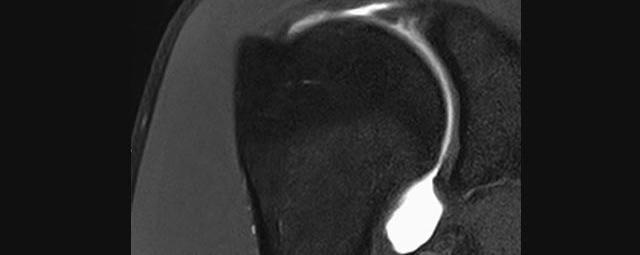

Gelenke

• Beurteilung von Knochen, Bändern und anderen Weichteilstrukturen der Gelenke nach Unfall.

• Arthrosediagnostik (Knorpelschaden)

• Impingement-Symptomatik

• Ursachenklärung bei wiederholter spontaner Gelenkluxation

• Ausbreitungsdiagnostik bei Gelenkentzündung, z.B. im Rahmen von rheumatischen Grunderkrankungen